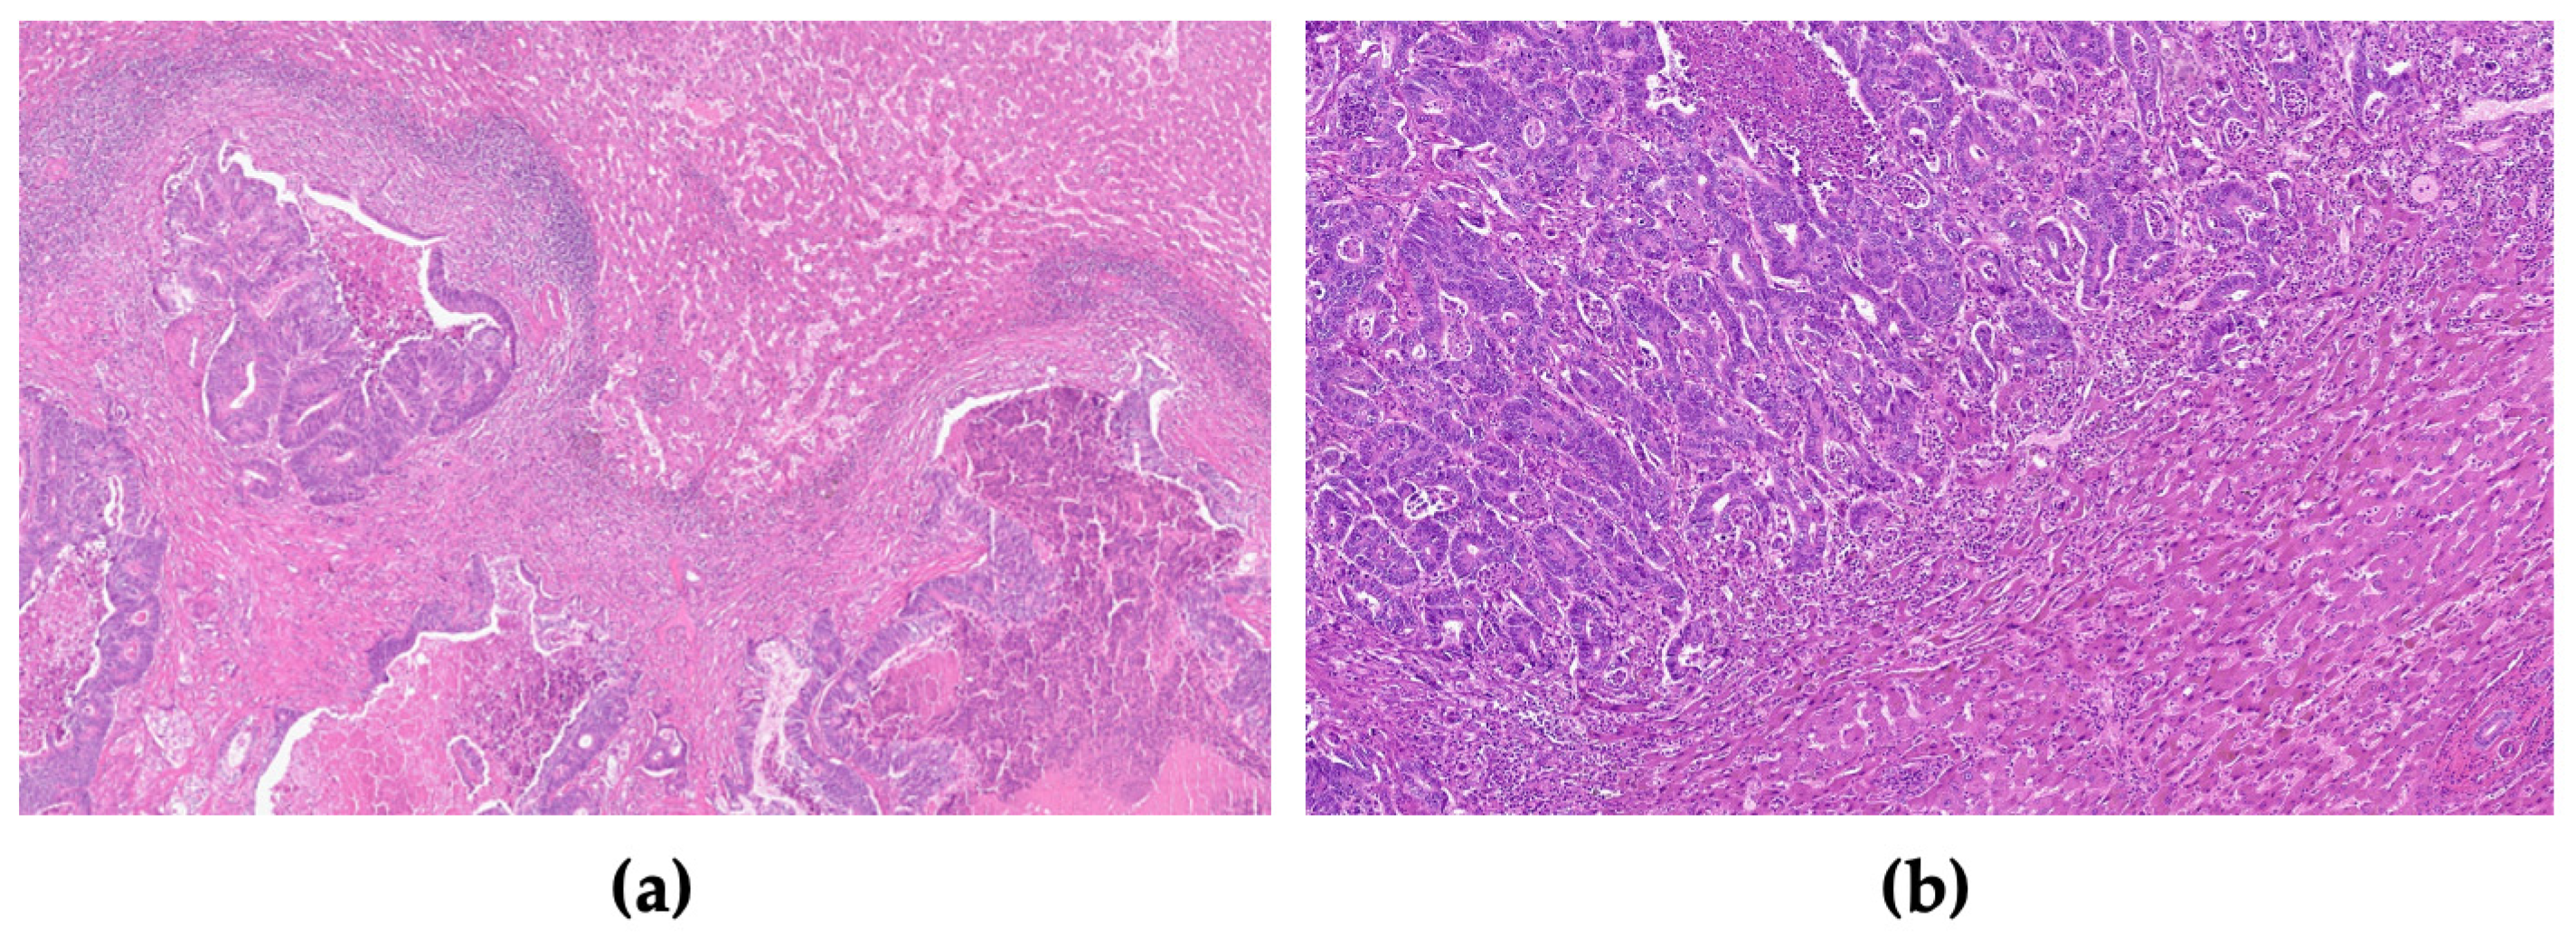

- Höppener, D.J.; Nierop, P.M.H.; Hof, J.; Sideras, K.; Zhou, G.; Visser, L.; Gouw, A.S.H.; de Jong, K.P.; Sprengers, D.; Kwekkeboom, J.; et al. Enrichment of the tumour immune microenvironment in patients with desmoplastic colorectal liver metastasis. Br. J. Cancer 2020, 123, 196–206. [Google Scholar] [CrossRef]

- Van Den Eynden, G.G.; Bird, N.C.; Majeed, A.W.; Van Laere, S.; Dirix, L.Y.; Vermeulen, P.B. The histological growth pattern of colorectal cancer liver metastases has prognostic value. Clin. Exp. Metastasis 2012, 29, 541–549. [Google Scholar] [CrossRef]

| Histologic growth pattern | |

| Desmoplastic | 17 (36) |

| Non-desmoplastic | 30 (64) |